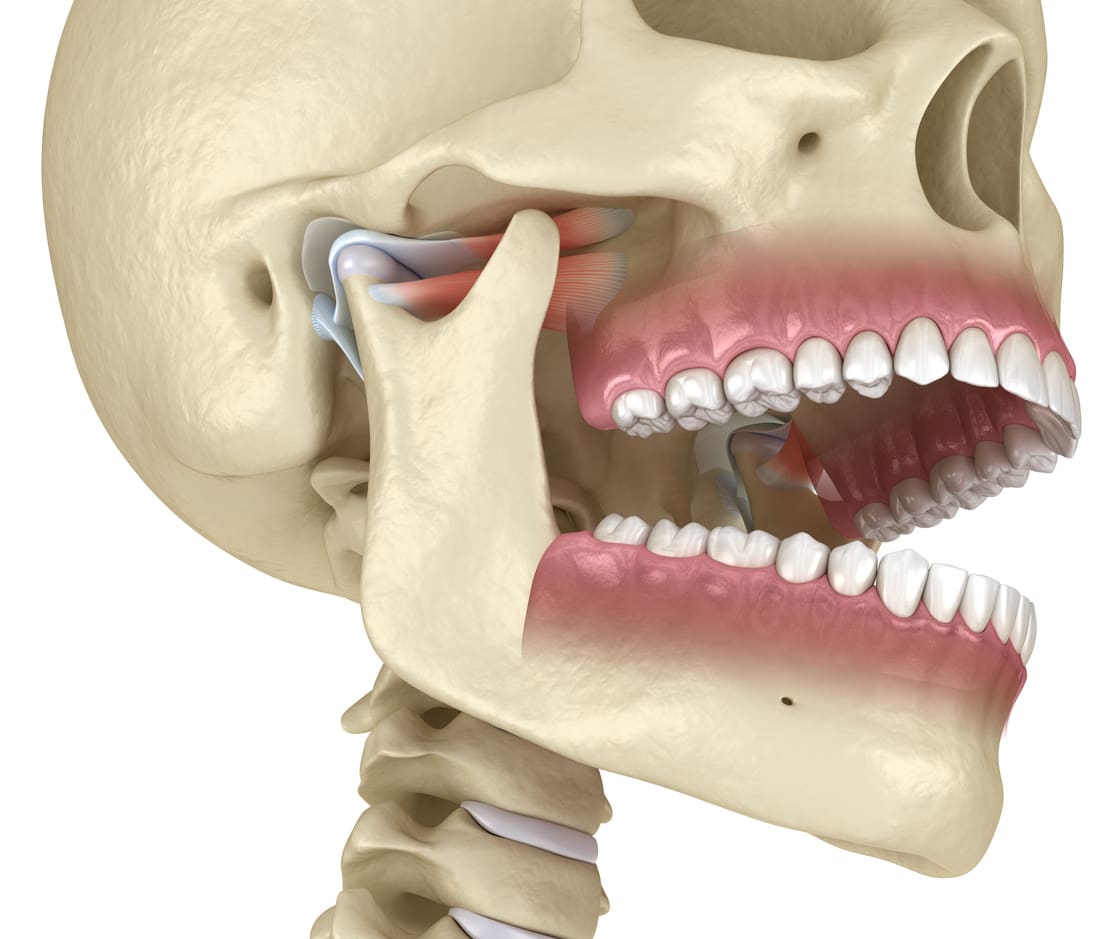

Rééducation maxillo-faciale : La rééducation maxillo-faciale est une discipline spécialisée qui traite les troubles fonctionnels de la tête, du cou et de la bouche. Cette thérapie est particulièrement utile pour les patients souffrant de problèmes de mâchoire, de douleurs faciales chroniques, de troubles de l’articulation temporo-mandibulaire, de problèmes de déglutition et de douleurs cervicales. La rééducation maxillo-faciale est souvent prescrite pour améliorer la qualité de vie des patients qui souffrent de ces troubles.

Nouvelle spécificité d’exercice qui aborde des pathologies jusqu’ici inaccessibles aux kinésithérapeutes. Découvrez comment vous pouvez traiter vos patients atteints des pathologies telles que les dysfonctions de l’articulation temporo-mandibulaire (ATM), pour des pathologies type rhinite chronique, otite, sinusite, SAOS (syndrome d’apnée obstructive du sommeil), troubles de la trompe d’eustache mais aussi acouphènes et vertiges (s’ils ne sont pas d’origine vestibulaire). En effet la rééducation maxillo-faciale cherche à atteindre 3 objectifs qui sont tout d’abord une position correcte de la langue, des lèvres, des joues au repos et lors de la déglutition (boire), de la phonation (parler) et de la mastication (manger).

Ensuite une respiration naso-nasale (seulement par le nez) qui est efficace avec une hygiène nasale correcte. Et enfin un équilibre musculaire et articulaire de l’ensemble de la zone oro-faciale (Crane, mâchoire et cervicales).